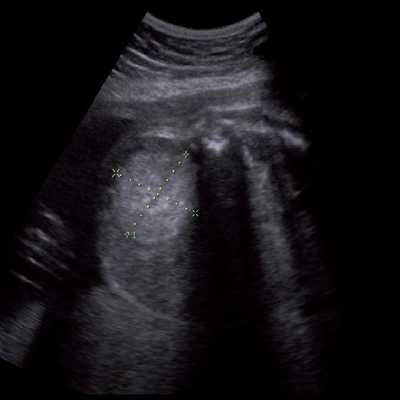

Под диафрагмой справа визуализировалось гиперэхогенное опухолевидное образование несколько неоднородной солидной структуры, с четкими ровными контурами, размером 50x38x35 мм. К нижнему полюсу данного образования прилежала правая почка, имеющая нормальные размеры, форму и структуру. Нижняя полая вена была смещена кпереди и влево. Обращала на себя внимание выраженная гепатомегалия, причем структура печени не была однородной. Она содержала множественные гиперэхогенные включения размерами до 17 мм, окруженные тонким гипоэхогенным периферическим ободком. Цветовое допплеровское картирование(ЦДК) демонстрировало интенсивную периферическую васкуляризацию опухоли (рис. 1-3).

Рис. 2. Кровоток в нейробластоме плода. Цветовое допплеровское картирование. Отчетливо виден питающий сосуд, огибающий образование по его периферии. К нижнему полюсу образования прилежит интактная почка плода.